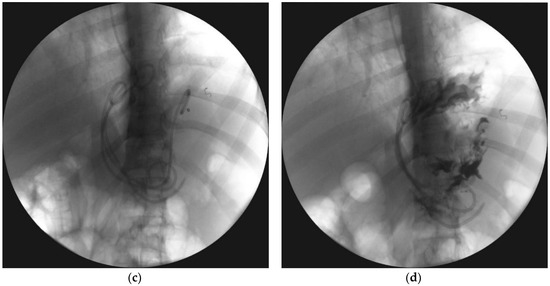

- Smoczyński, M.; Jagielski, M.; Jabłońska, A.; Adrych, K. Endoscopic necrosectomy under fluoroscopic guidance- a single center experience. Wideochir. Inne. Tech. Maloinwazyjne. 2015, 10, 237–243. [Google Scholar] [CrossRef] [PubMed]

- Jagielski, M.; Smoczyński, M.; Adrych, K. Transpapillary drainage of pancreatic parenchymal necrosis. Wideochir. Inne. Tech. Maloinwazyjne 2015, 10, 491–494. [Google Scholar] [CrossRef]

- Smoczyński, M.; Jagielski, M.; Jabłońska, A.; Adrych, K. Transpapillary drainage of walled-off pancreatic necrosis- a single center experience. Wideochir. Inne. Tech. Maloinwazyjne 2015, 10, 527–533. [Google Scholar] [CrossRef] [PubMed]

- Smoczyński, M.; Jagielski, M.; Siepsiak, M.; Adrych, K. Endoscopic necrosectomy through the major duodenal papilla under fluoroscopy imaging. Arch. Med. Sci. 2018, 14, 470–474. [Google Scholar] [CrossRef] [PubMed]

| Passive transpapillary drainage | The insertion endoscopic pancreatic stent to pancreatic duct through duodenal papilla. |

| Active transpapillary drainage | Endoscopic insertion pancreatic endoprosthesis as well as nasal drain to pancreatic duct through duodenal papilla. |